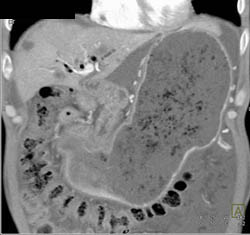

Diagnosis

Antral Carcinoma